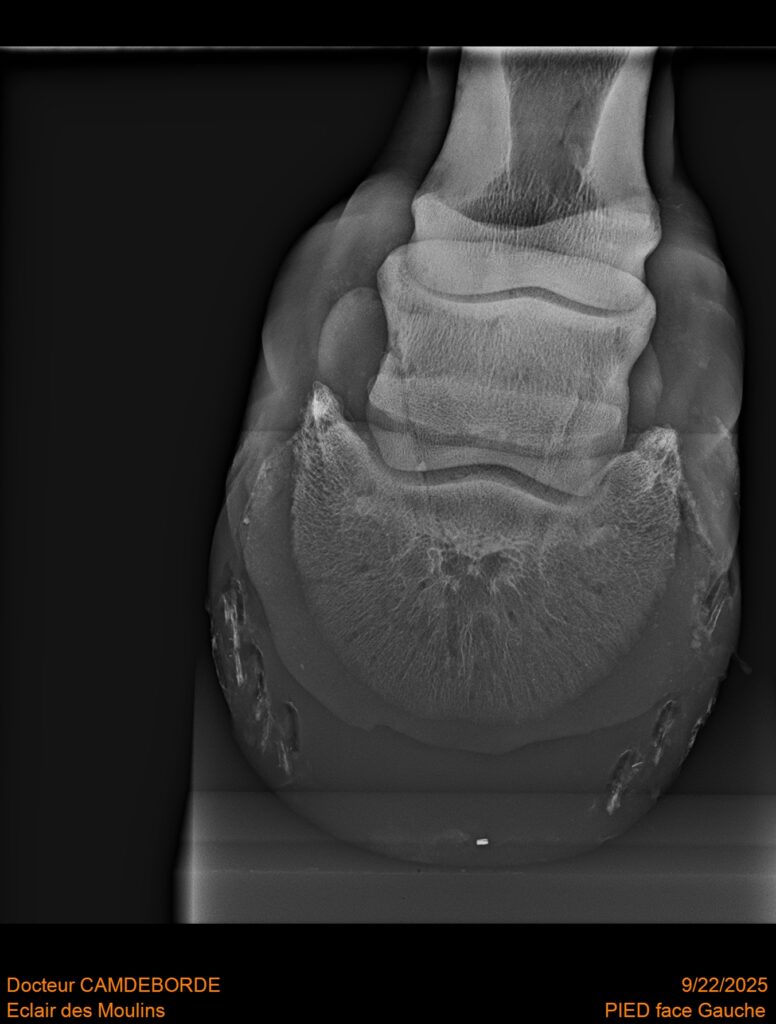

RADIOS ET CLINIQUE